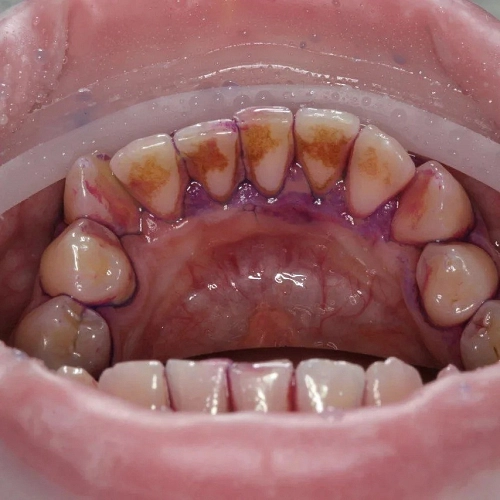

Как понять, что пора на профессиональную гигиену полости рта

На необходимость профгигиены указывают:

кровоточивость десен любой степени, покраснение десневых сосочков, зуд и боль в деснах (все эти симптомы обусловлены отложением камня под десной)

ощущение шероховатости зубов и пломб

появление или усиление повышенной чувствительности зубов

наличие зубного камня, пигментированного налета на зубах

застревание пищи между зубами, невозможность продеть зубную нить

неприятный запах изо рта.